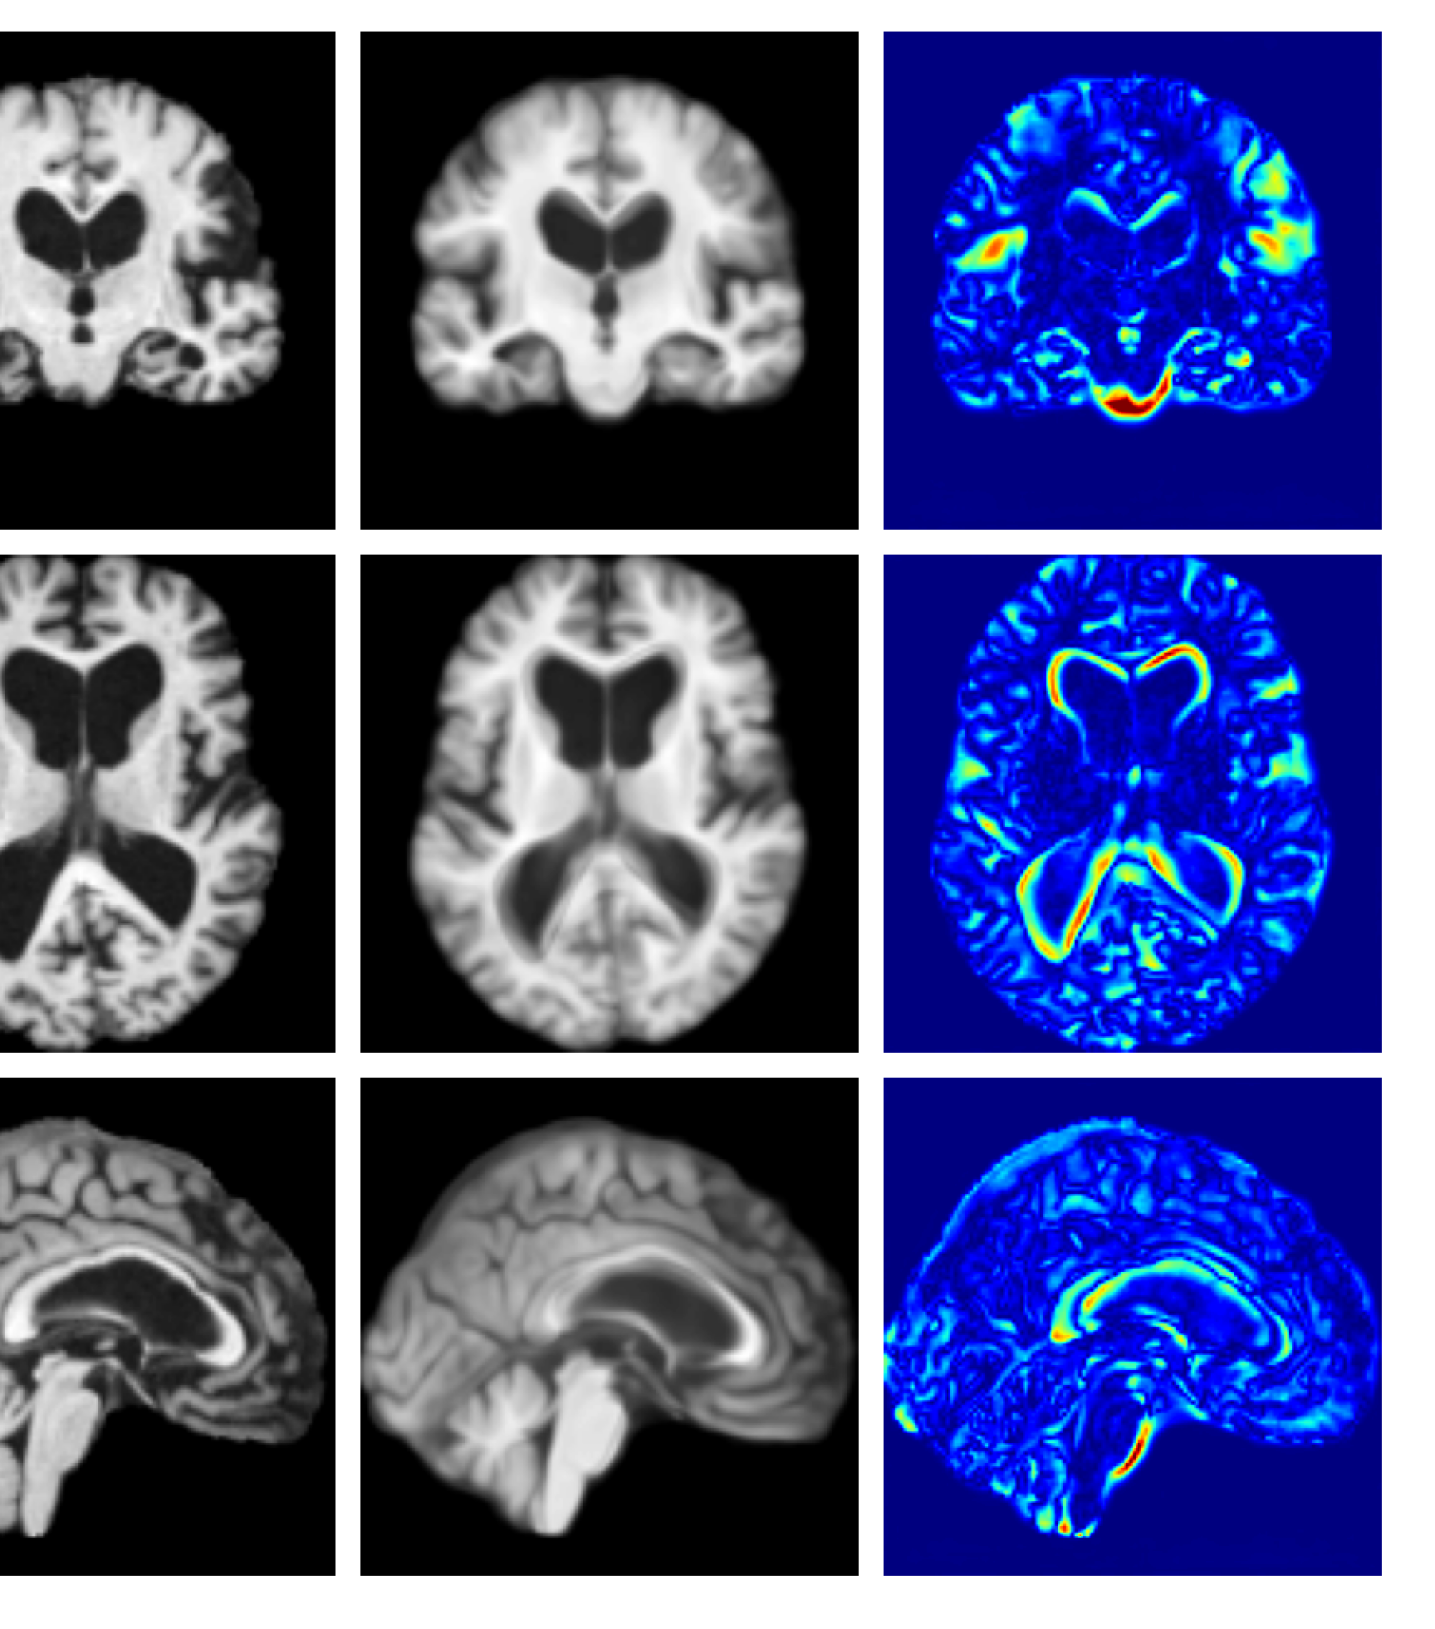

Refer to caption

(a) Input

Figure 10: Example reconstructions and anomaly maps for an AD sample from the disease cohort of the ADNI dataset. We expect to see some inpainting of atrophied tissue whilst retaining the defining characteristics of the individual sample.